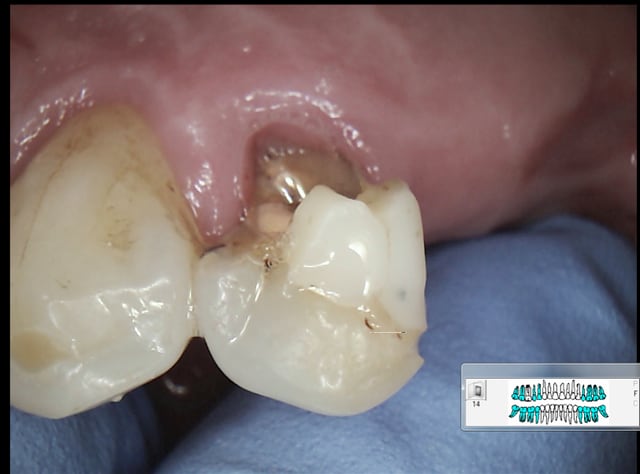

RTE ! -))) Et IC coiffes dans la foulée non mais ! On peut meme se payer le luxe d' etre pulpo conscient et résister à dégainer le R25 en faisant un petit compo offert dans la foulée ! ( 24)

Endo de merde rime avec SC 33 de merde, endo de qualité rime avec inlay core, ca vous étonne ? Dur dur de gagner sa vie avec des soins opposables en les faisant correctement, hein ?-))))

Alors RTE ou pas RTE ( meme patient) ? Pas trop mal cette endo, on est jamais à l'abri d'un coup de bol ! -))))

La prothèse c'est pas mon truc. Mais dans le temps imparti pour faire le tt de A à Z l'expérience montre qu'il faut en consacrer le plus pour l'endo. -))))